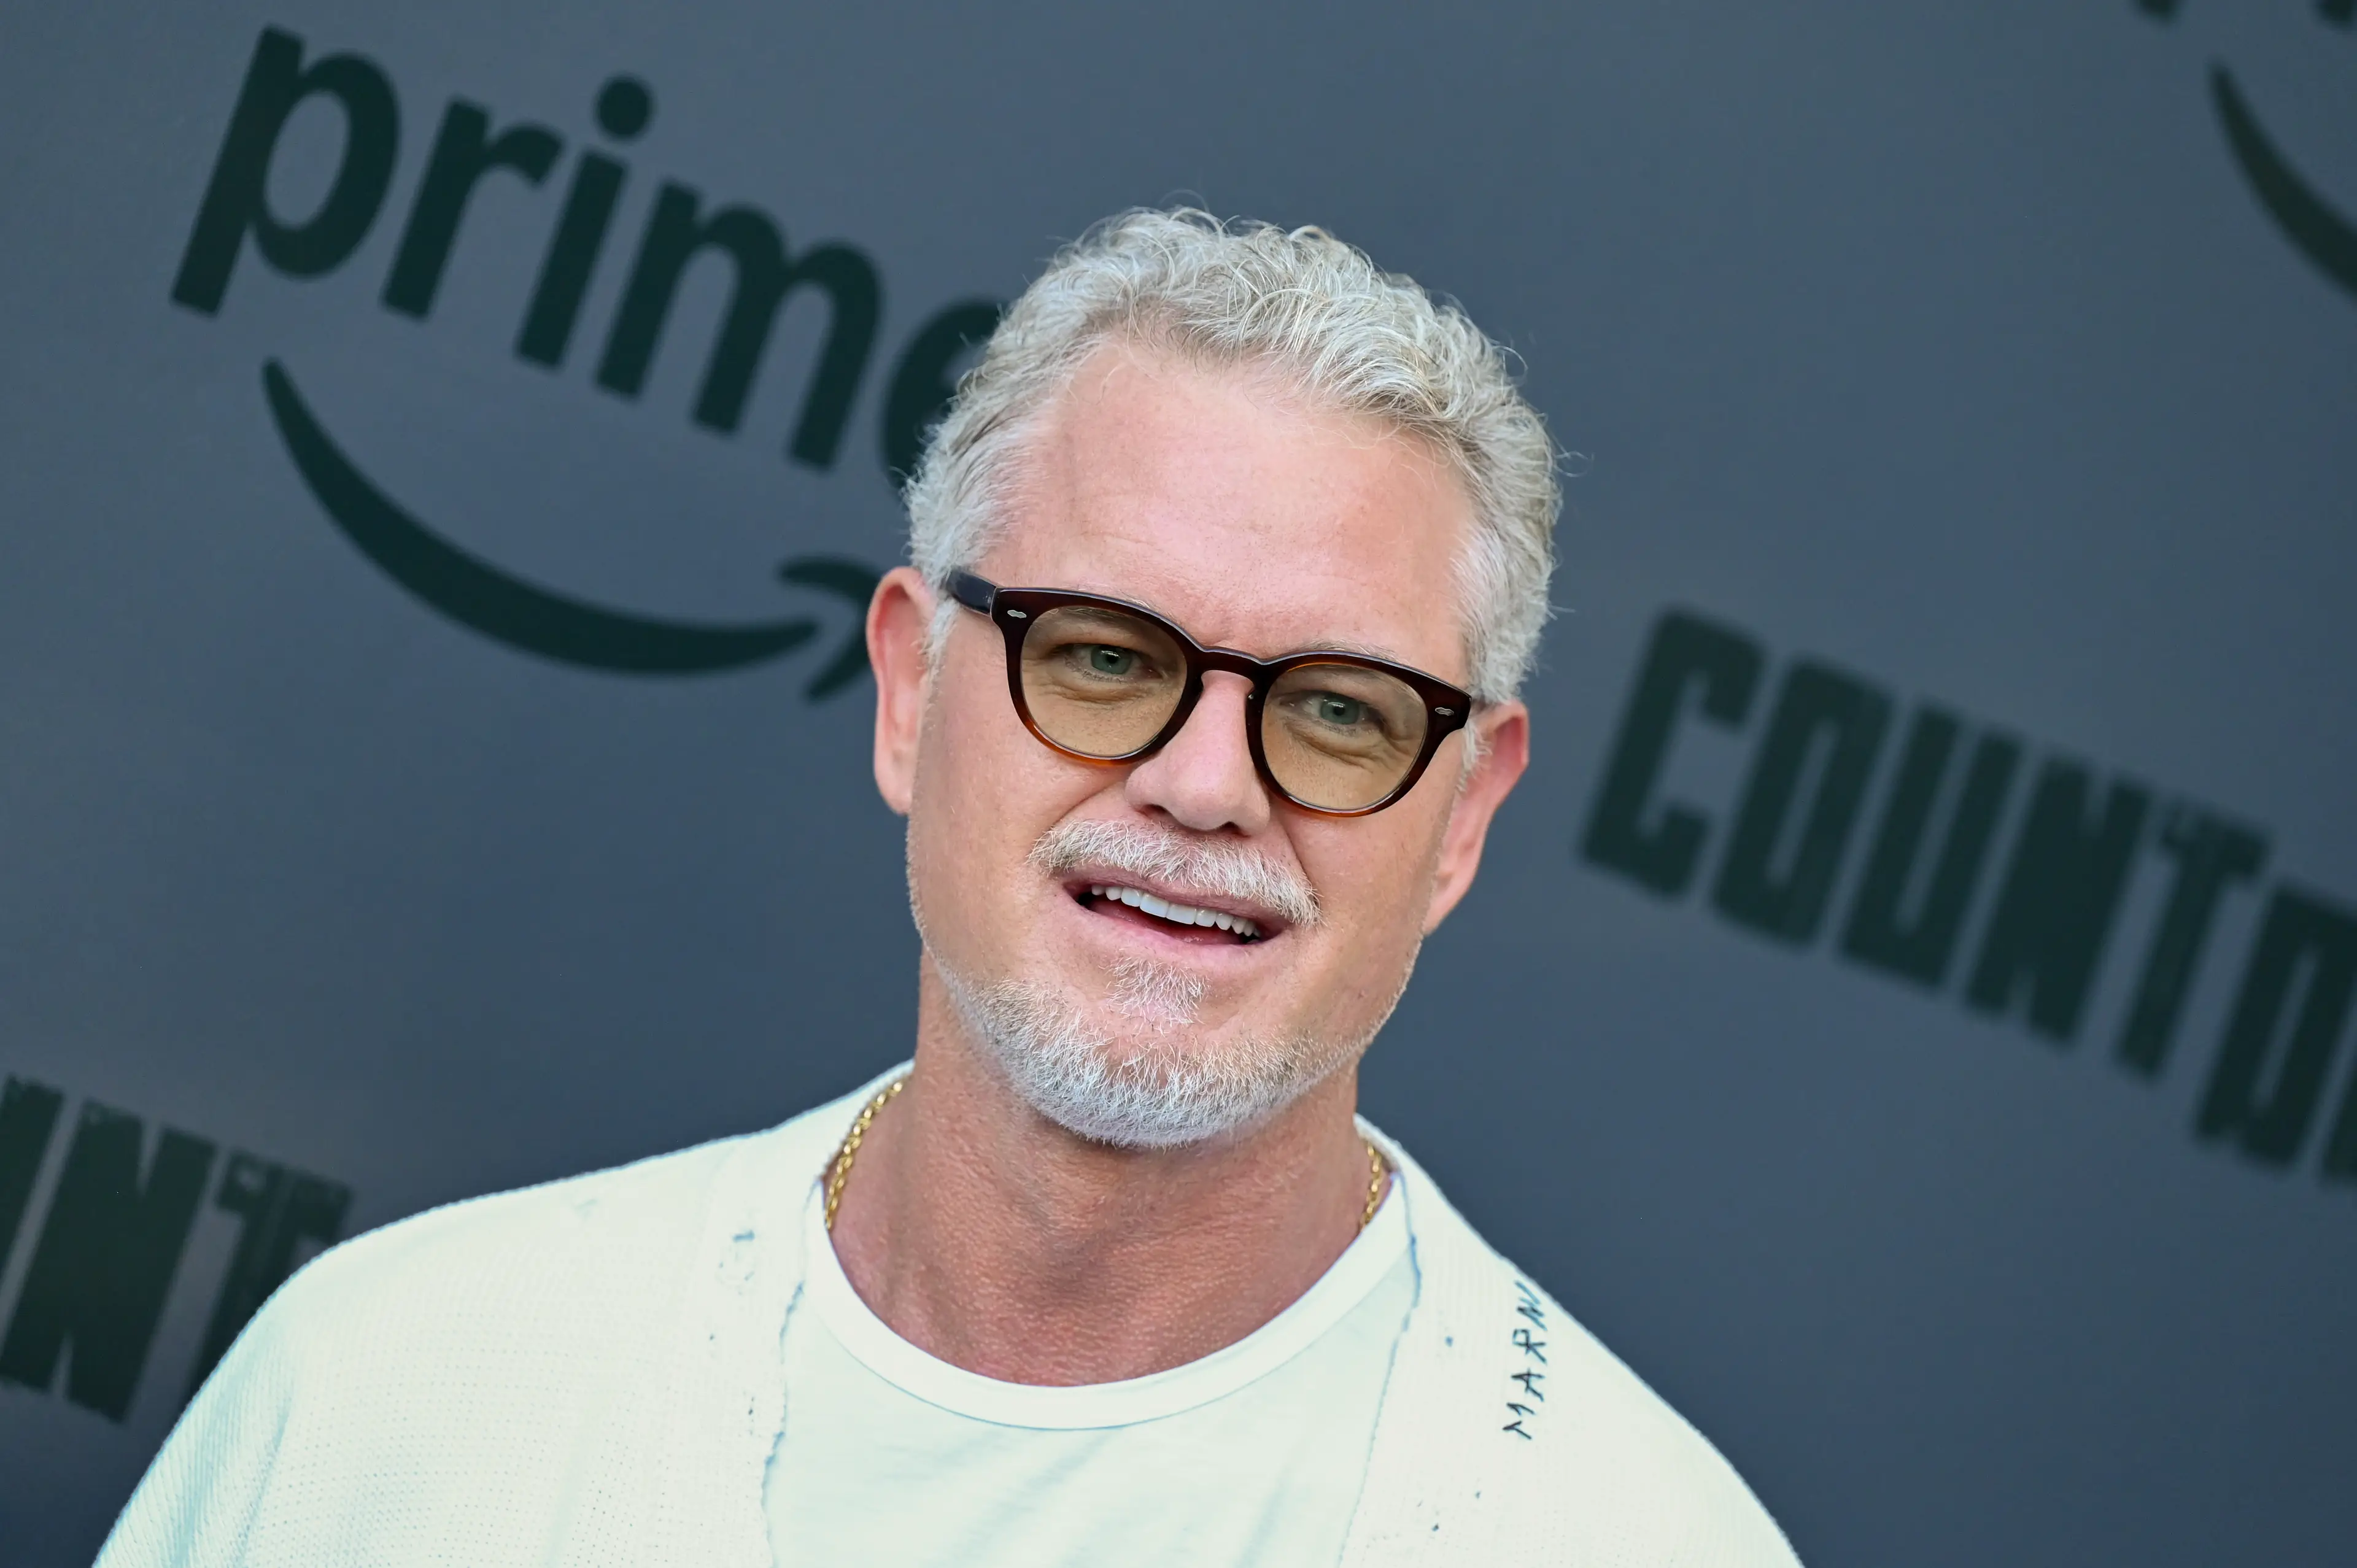

Grey’s Anatomy star Eric Dane, who passed away from ALS aged 53 on Thursday (February 19), is remembered as a passionate advocate for patients with the disease as much as his TV and film roles.

Late on Thursday evening, Dane’s representatives confirmed he had sadly died some ten months after he went public with his diagnosis.

“With heavy hearts, we share that Eric Dane passed on Thursday afternoon following a courageous battle with ALS. He spent his final days surrounded by dear friends, his devoted wife [actress Rebecca Gayheart] and his two beautiful daughters, Billie and Georgia, who were the center of his world,” the statement said.

Eric Dane has died aged 53 (Nathan Congleton/NBC via Getty Images)

“Throughout his journey with ALS, Eric became a passionate advocate for awareness and research, determined to make a difference for others facing the same fight. He will be deeply missed, and lovingly remembered always. Eric adored his fans and is forever grateful for the outpouring of love and support he’s received. The family has asked for privacy as they navigate this impossible time.”